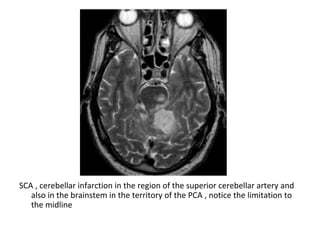

2-Superior Cerebellar Artery (SCA in grey)

-The SCA territory is in the superior and tentorial

surface of the cerebellum

SCA , cerebellar infarction in the region of the superior cerebellar artery and

also in the brainstem in the territory of the PCA , notice the limitation to

the midline